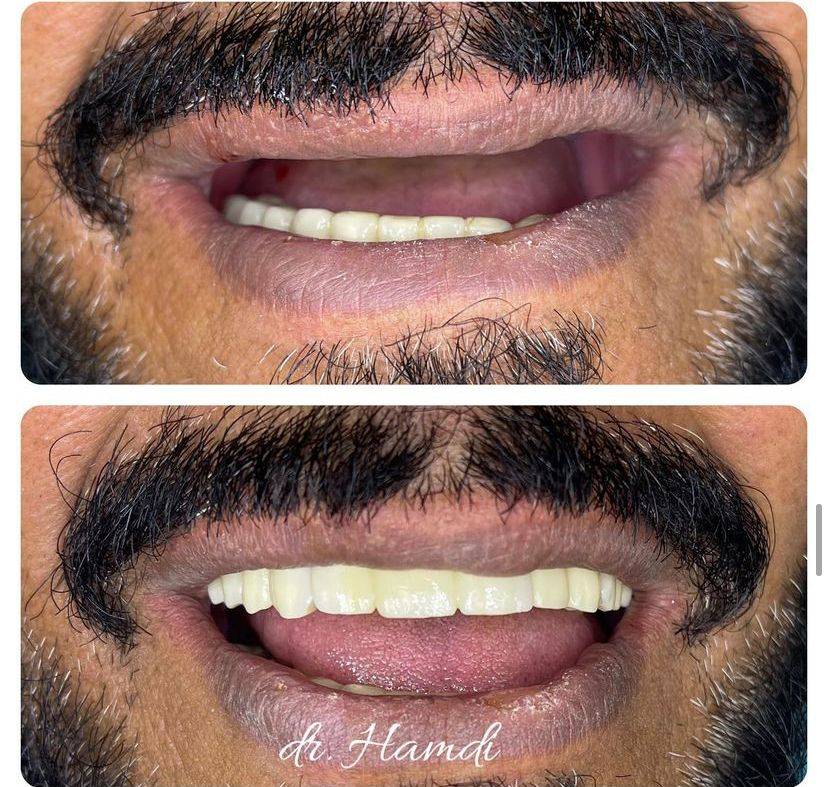

الدكتور حمدي العوضي

تخرج الدكتور حمدي العوضي من كلية طب الأسنان في عام 2003 ، وأنهى فترة تدريبه ، وعمل على الفور في مستشفى اليمامة (وزارة الصحة) حيث عمل كممارس أسنان عام لمدة 4 سنوات.

أجرى الدكتور حمدي العوضي أكثر من 50.000 عملية زراعة أسنان وترقيع عظمي خلال السنوات العشر الأخيرة من ممارسته.